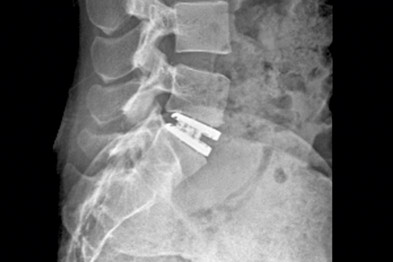

Polymethylmethacrylate(PMMA) Augmentation Of ... - IOSR Journals

Lumbar degenerative disease is common in the elderly people, patients often associated with severe Mainly for degenerative lumbar degenerative disc bulging or protruding, facet hypertrophy, yellow ligament hypertrophy, ... View Doc